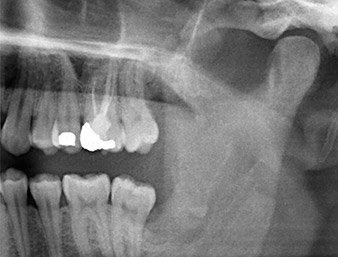

Ya en la ortopantomografía, se constató que había un resto radicular de la región 38 muy cerca del nervio alveolar inferior (figura 1). La raíz se había fracturado durante la osteotomía, pero el primer odontólogo que había tratado al paciente no había extraído esta debido a la presencia de dolor durante la operación.

Ortopantomografía

Imagen 1: Ortopantomografía 6 meses después de la osteotomía del diente 38: el resto radicular se encontraba cerca del nervio alveolar inferior.

En la imagen en 3D (tomografía volumétrica digital) se constató que el resto radicular se encontraba muy desplazado en sentido distocaudal en la transición situada entre la porción horizontal y la ascendente del maxilar inferior (figura 2).

TVD transversal

Imagen 2: Representación de una TVD transversal del resto radicular en el espacio retromolar.

La anamnesis del paciente era favorable (no fumador, 26 años) para garantizar el éxito de la aplicación. Como la ortopantomografía mostró que el resto radicular se encontraba muy cerca del nervio alveolar inferior, se realizó también una tomografía volumétrica digital (6).